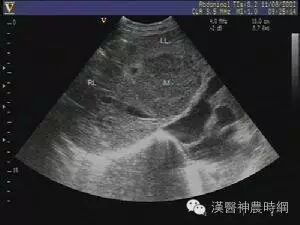

1.超声检查  B超检查用于肝癌诊断具有无损伤、无放射损害、简便、价廉、敏感度高、可重复性等优点。它可显示肿瘤的大小、形状、部位、肿瘤与血管的关系以及肝静脉、门静脉有无癌栓等,其诊断符合率可达90%。B超可检出1~2cm的小肝癌,最小直径为0.5~0.7cm。文献报道高分辨力B超对0.5~2.0cm的肝内微小灶的发现率较高,但定性诊断的准确率仅为58%。近年国内外均有人采用超声对比剂,如铁或钆等行声学造影,有助于定性诊断和确定病灶大小。原发性肝癌B超图像常显示肝体积增大,病变向肝表面隆起,周围常有声晕等。其回声可表现为低回声型、高回声型和混合回声型。小肝癌常呈低回声型,大肝癌或呈高回声,或高低回声混合,并可见中心坏死液化的无回声区。B超检查可因肺、胃等器官遮盖存在盲区,造成遗漏病变,如右膈下、左外叶上段等。微小病变位于肝实质深部并伴有严重肝硬化时,常难以辨认。另外与操作者的经验和检查是否细致均有关。